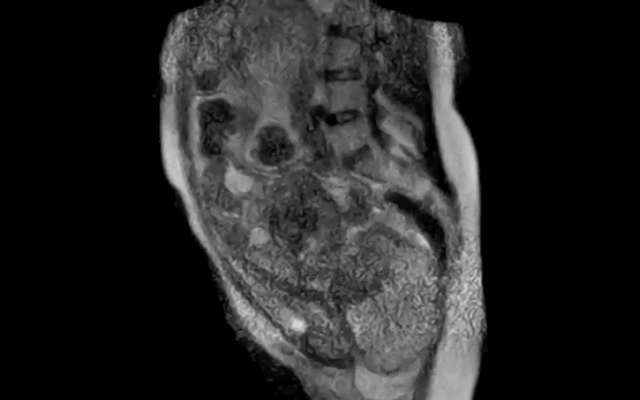

Quay lại với ca sinh nở, các nhà khoa học tại Bệnh viện Đại học Charité, Berlin, Đức đã ghi lại 45 phút cuối của quá trình chuyển dạ , sau đó rút gọn thành một đoạn video dài 25 giây. Hình ảnh cho thấy rõ vị trí thai nhi, sự di chuyển của em bé qua ống sinh và sự thay đổi của các cơ quan trong cơ thể người mẹ khi rặn sinh.